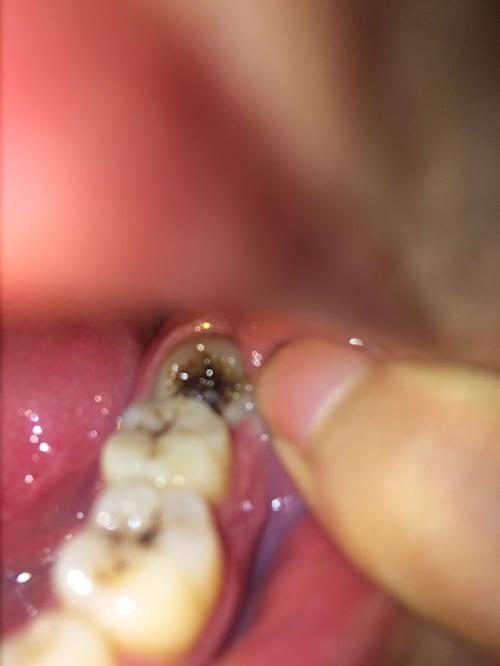

拔智齿干槽症

拔完智齿干槽症图片

智齿旁边的肉肿图片

干槽症的牙洞是啥样的

拔牙一周后牙窝槽样子

干槽症牙洞

拔牙10天后牙窝状态图

干槽症早期症状图片

干槽症牙洞颜色

拔牙后的血凝块图片

拔牙血凝块白色假膜图

干槽症伤口颜色

典型干槽症图片

干槽症伤口图片